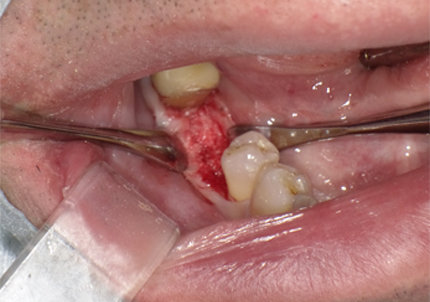

6.二次手術

インプラント周囲の角化歯肉(付着歯肉:骨に固定されてる歯肉)の獲得を目的に歯肉弁を移動する